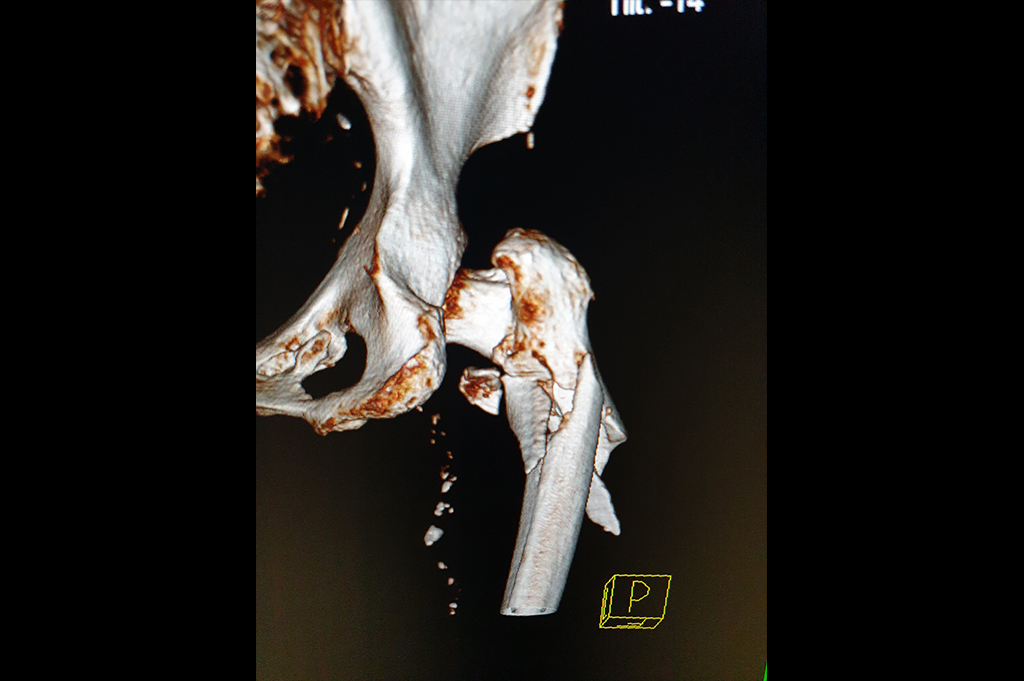

Subtrochanteric Fracture

Periprosthetic Fracture THR